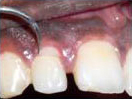

Labial Soft Tissue

Reflected

Palatal Soft Tissue